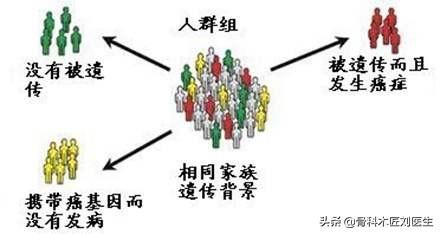

3つ目は、私たちが変えることのできない遺伝的要因である。時々、私たちは家族が癌や腫瘍になるのをよく見たり聞いたりするが、実はこれには遺伝的要因が関与している。家族の父親か母親が胃がんにかかると、その子供の子孫に胃がんのリスクが高まるが、これは主にいくつかのがん遺伝子の不活性化が関係している。浸潤性胃癌の家族性傾向はより顕著である。さらに、胃がん患者の10%は家族歴があり、胃がんの家族歴がある集団に比べて発症率は2~3倍高い!

第二に、食生活が良好で、同時に胃がんが発見されたカップルは「運命づけられている」可能性がある。胃がんは、生活習慣や食習慣の悪さに加えて、実は遺伝することもある。例えば、日本人は胃がん患者が異常に多い。そして、ナポレオンの例もあるが、彼の父親、祖父、3人の姉妹はすべて胃がん患者だった!つまり、夫婦が同時にがんにかかるというのは、本当に「運命」なのかもしれないし、誰もが胃がんの遺伝歴を持っているのかもしれない。

第三に、この夫婦には遺伝的な素因がある可能性が高いと思う。実はこれは、1つ目と2つ目のポイントの「キャッチボール」である!夫婦ともに胃がんの遺伝的背景があり、もともと胃がんのリスクが高い。そして同時に、食生活や生活習慣が悪い!このような家庭で育つ子供たちは、胃がんの予防と治療にもっと注意を払う必要がある!

また、がんはB型肝炎などの伝染病と同じように伝染すると思われがちで、家族間の恐怖心を煽りやすい。 実際には、がんは人に伝染することはないが、家族間で遺伝する傾向があるため、友人同士で心配する必要はない。

夫婦が同じ種類のがんに罹患する可能性というと、明らかに別人なのに、どうして同時にがんに罹患するのだろうと不思議に思われる方も多いかもしれませんが、実はこのような現象は珍しいことではありません。実は、このような現象は決して珍しいことではなく、私たちの臨床の現場でも、「夫婦がん」や「家族がん」、特に「家族がん」と呼ばれる、一家に何人も同じ種類のがんにかかるケースによく遭遇します。特に "家族がん "は、家族で同じ種類のがんにかかる人が続出し、人々は絶望することが多い。その理由はどこにあるのでしょうか?